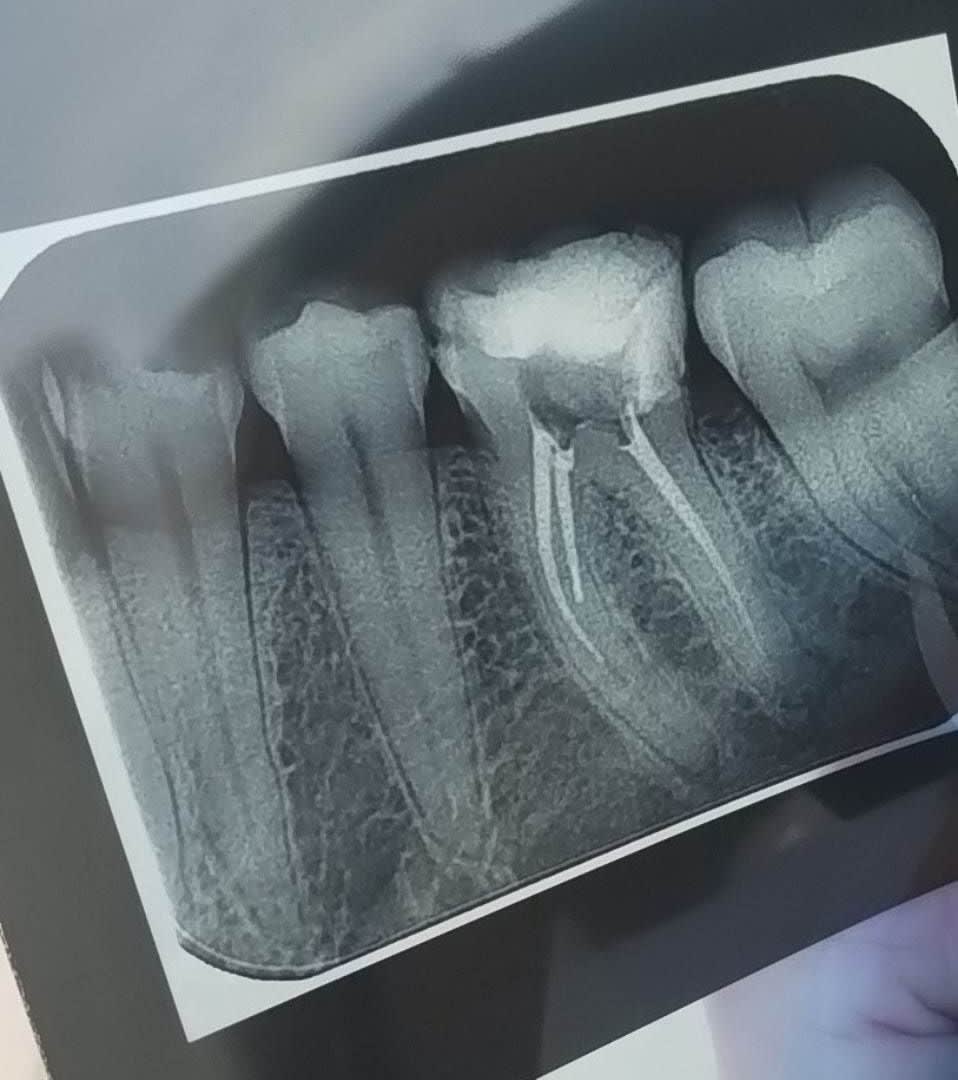

Resultat de mon endo

Lime endomoteur casse MV :s

Et finalement en distal c'était surement de l'hydroxyde de calcium car ça a plus ou moins disparu !!

(2seances d'hydroxyde de calcium, chaque seance irrigation Hypo, toujours sous digue, d'où la décision de laisser la Lime en place, la patiente est informée et rassurée)

Obturation composite direct